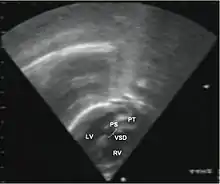

•Echocardiogram: An echocardiogram is an ultrasound of the heart that accurately assesses the heart’s structure and function, and can show the specific features of TGA, if present. This imaging modality allows for the definitive diagnosis of TGA to be made.[3]

Abbreviations: LV and RV=left and right ventricle, PT=pulmonary trunk, VSD=ventricular septal defect, PS=pulmonary stenosis.